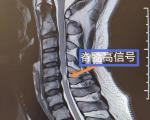

另外一点是腰间盘突出,是因为坐骨神经长期受到压迫而导致的感觉,如果遇到这种情况,千万要及时进行治疗,不然很有可能会慢慢扩张到腿部,严重的话可能会影响行动。